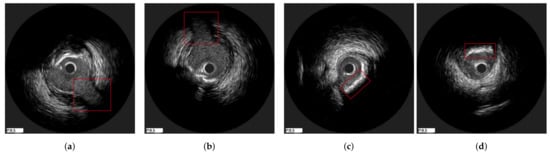

3.3. Axial Registration

3.3.1. Mutual Information